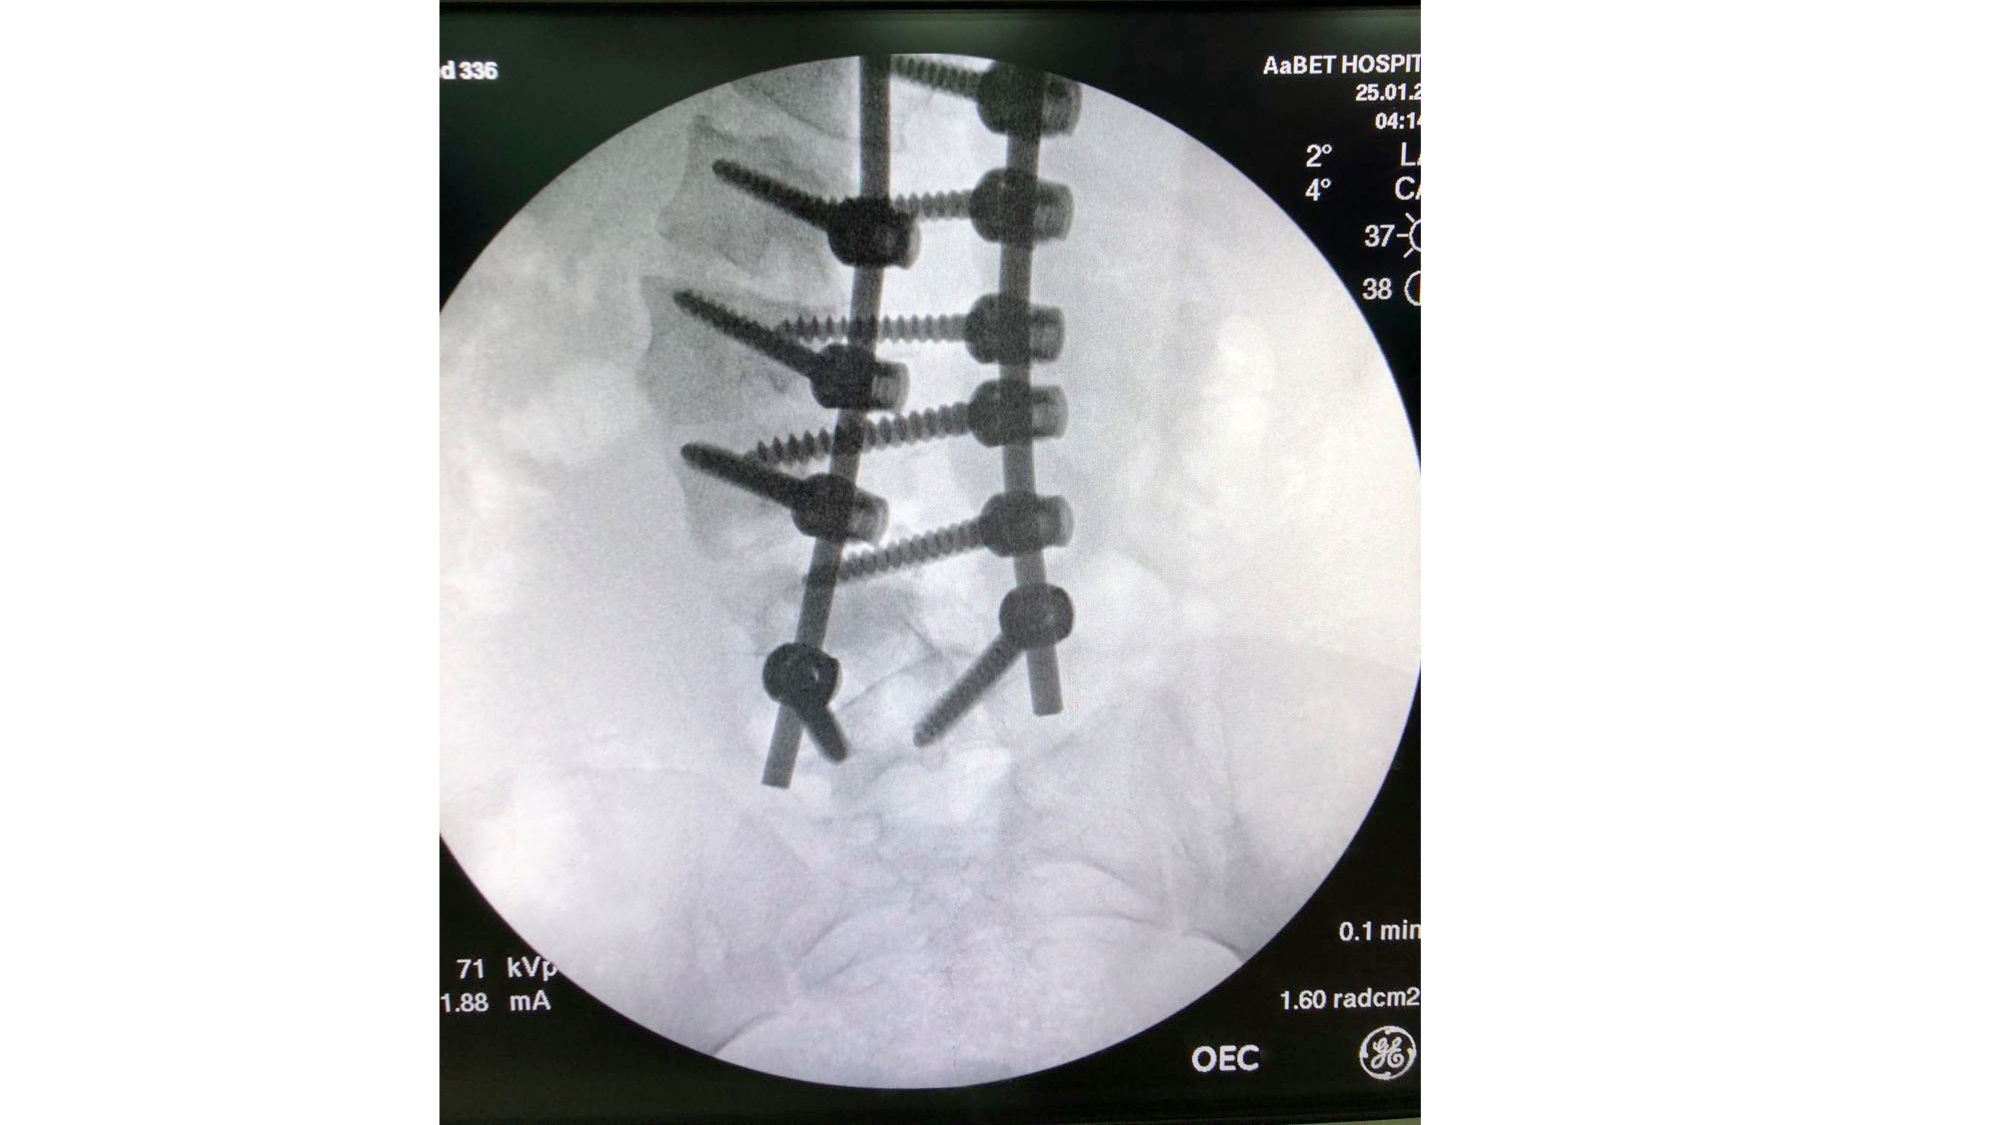

I was also able to meet the first two spine surgery fellows at AaBET. They are both neurosurgeons. The plan after next year is to alternate orthopedic with neurosurgery spine fellows. In addition to their teaching at AaBET, they are mentored by Dr Fasil Mesfin of Univeristy of Missouri, with whom they have weekly cases conferences. They were excited to show me two massive spine tumors they just operated on, one a giant, dumbbell shaped neurofibroma of the lower thoracic spine with bone involvement and preoperative paraparesis; the other a huge aneurysmal bone cyst of posterior lumbar element. Both needed pedicle screw instrumentation and big exposures. I am not a spine surgeon but the operative photos and postop xrays were very impressive.